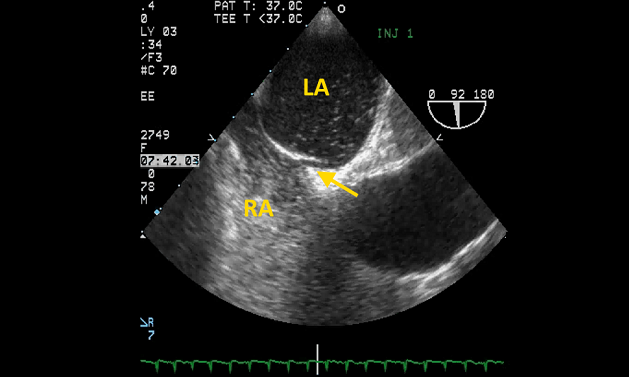

Additionally, Pristipino said the task force focused heavily on best practices for PFO diagnosis in the first place. Transesophageal echocardiography (TEE) has long been the “gold standard” for diagnosing PFO, he observed, “but unfortunately and deceivingly we found that in fact that the sensitivity of the technique is much less than what we thought before.” Therefore, the task force recommends contrast-enhanced transcranial Doppler as a first-line test to detect a right-to-left shunt, because of its high sensitivity. Transthoracic echo can be used as a first-line test, Pristipino clarified, noting that transcranial Doppler should be done afterwards if TTE is negative or equivocal. TEE should be used in all cases in which it is necessary to rule out embolic sources other than the PFO and to assess the anatomical features of a PFO, the authors state.